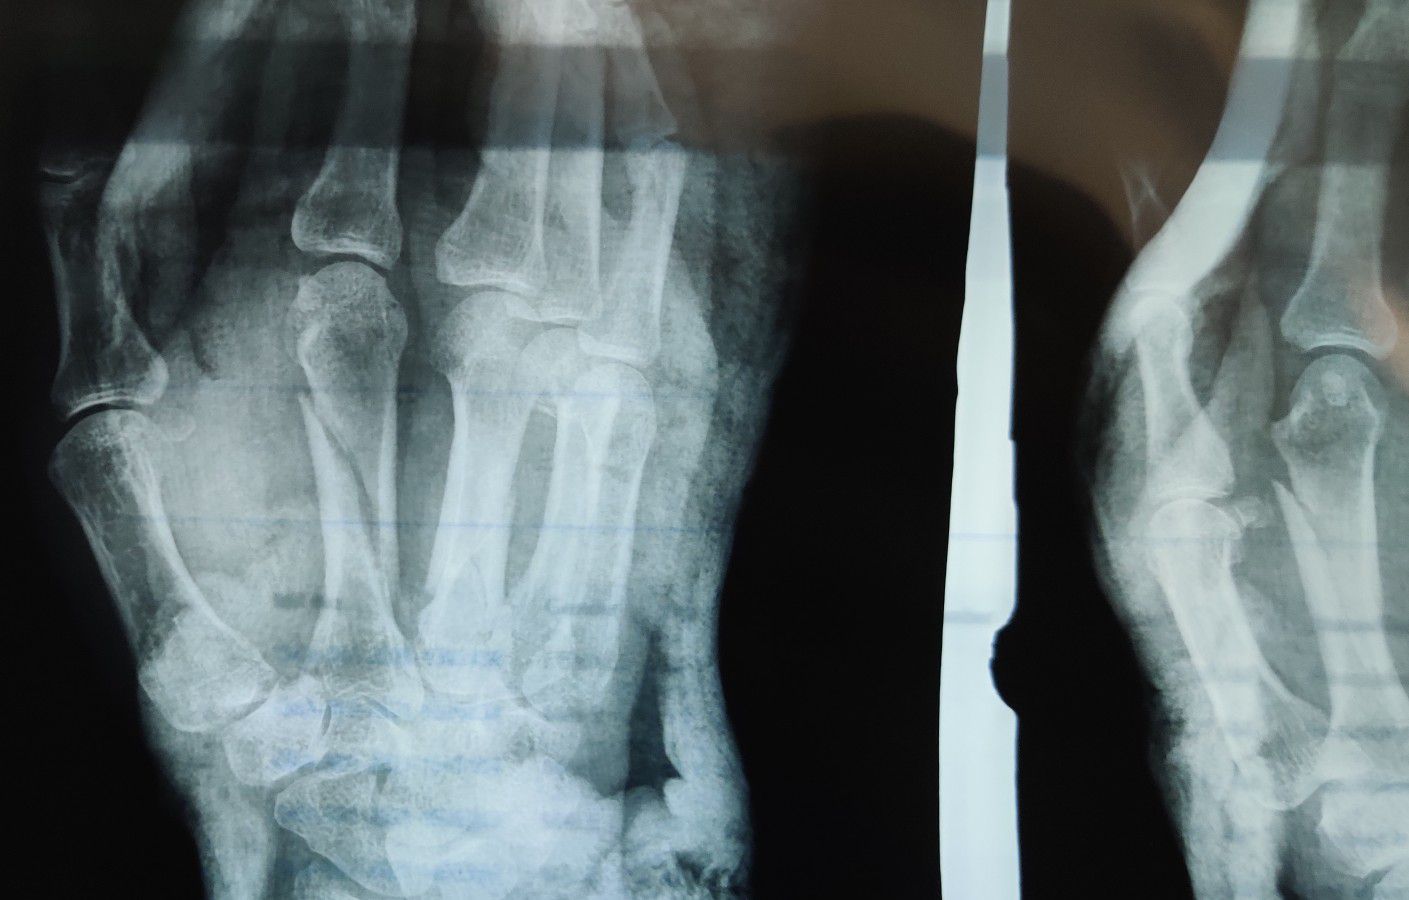

Fracture 2nd Metacarpal

Orthopaedics

Fracture

Metacarpal